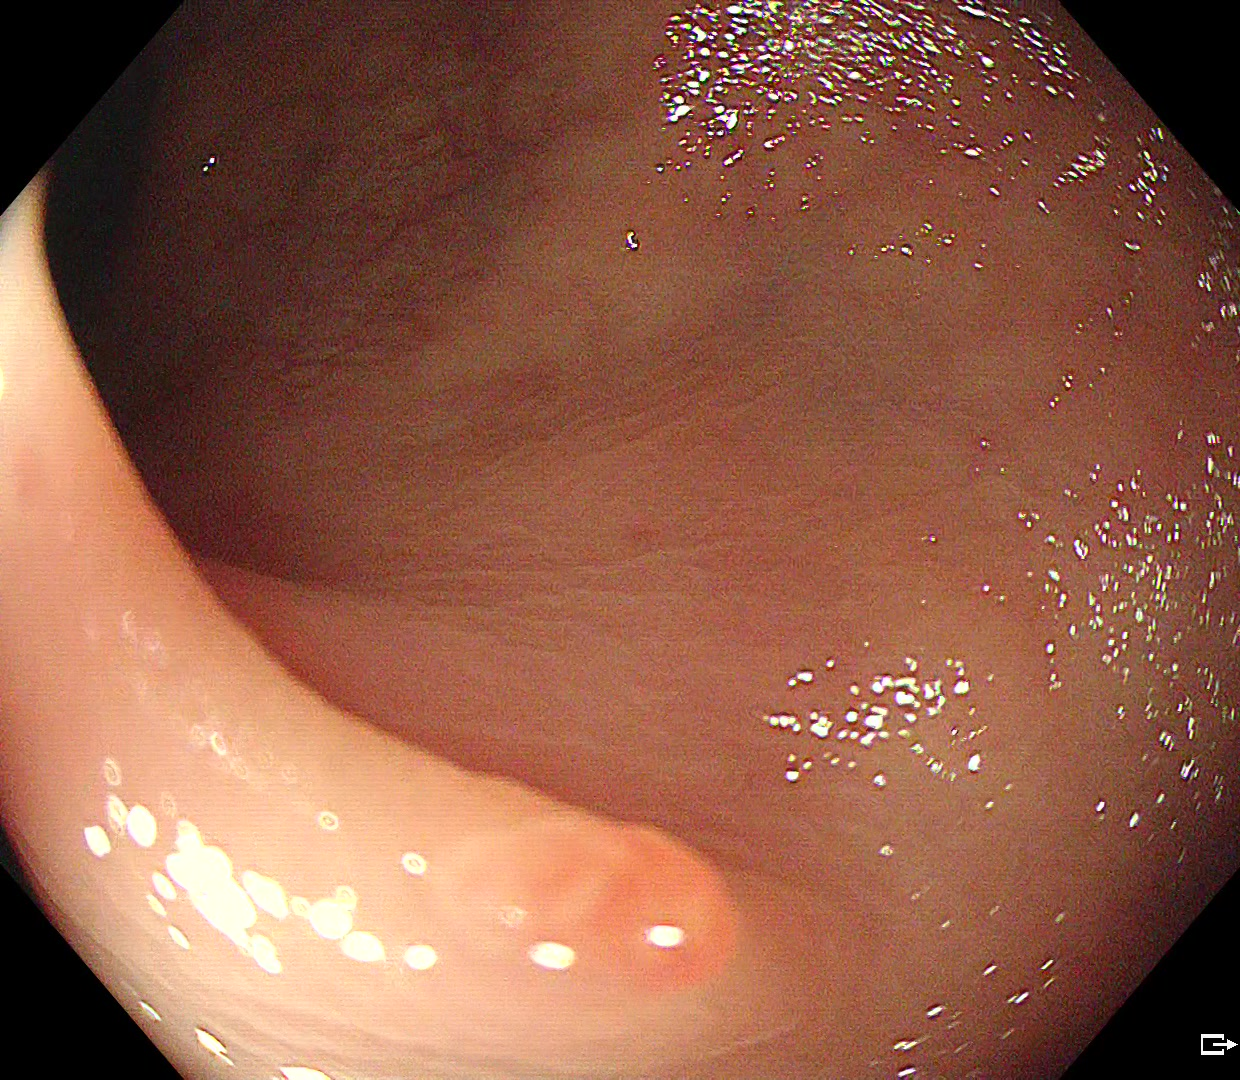

Endoscopy